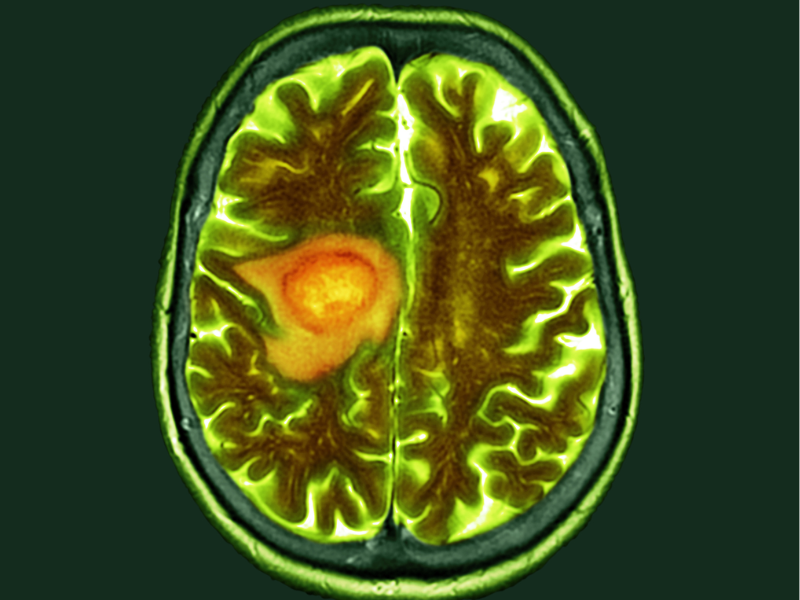

Glioblastoma, a highly resistant cancer, often results in survival periods of under two years after diagnosis. In a recent NPJ Genomic Medicine study, scientists from the University of Notre Dame discovered that a relatively overlooked cell might provide fresh understanding regarding how this aggressive form of brain cancer eludes immunotherapy.

Their exploration led to an unexpected discovery: the identification of a relatively new cell type known as perivascular fibroblasts. Normally found in healthy brain blood vessels, these fibroblasts play a role in depositing collagen to maintain the structural integrity and functionality of brain vessels.

Analyzing their data, researchers categorized patients into two groups based on the prevalence of perivascular fibroblasts within their tumors. The study found that patients with a higher proportion of these fibroblasts responded less favorably to immunotherapies and exhibited poorer survival rates.

Further exploration uncovered that perivascular fibroblasts play a crucial role in establishing an immunosuppressive environment within the tumor, aiding the cancer’s evasion of the immune system. Additionally, these fibroblasts potentially contribute to the cancer’s resistance to therapies, such as chemotherapy, by promoting stem-like cancer cells that exhibit low division rates, known as a key factor in tumor relapse and spread.

Datta suggests that perivascular fibroblasts, a part of the brain’s healthy vasculature, may be migrating or infiltrating glioblastoma tumors. However, instead of supporting normal brain function, these fibroblasts undergo reprogramming, aiding the tumor’s growth.